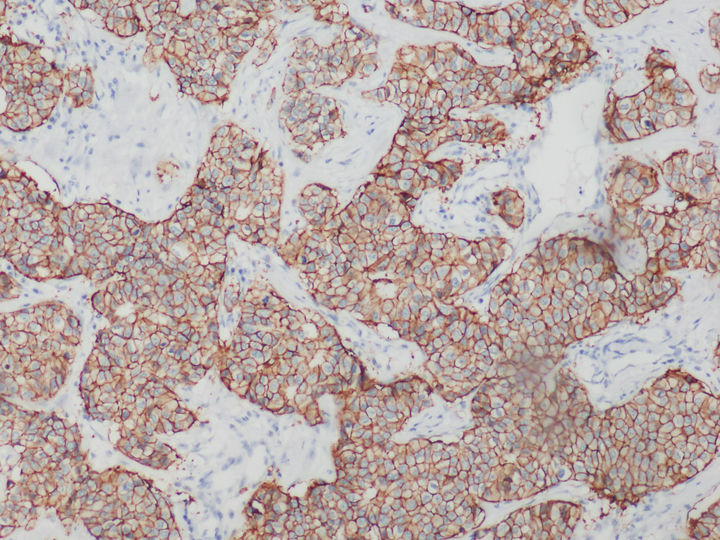

荧光显微镜下的乳腺癌HER2检测

在乳腺癌,胃癌等肿瘤筛查领域中,HER2的表达水平是肿瘤检测的常用指标。目前,HER2基因检测常见方式以免疫组化IHC技术和FISH技术为主。

免疫组化HER2检测可以用普通显微镜明场观察实现,设备要求较低,但灵敏度和特异性相对弱。